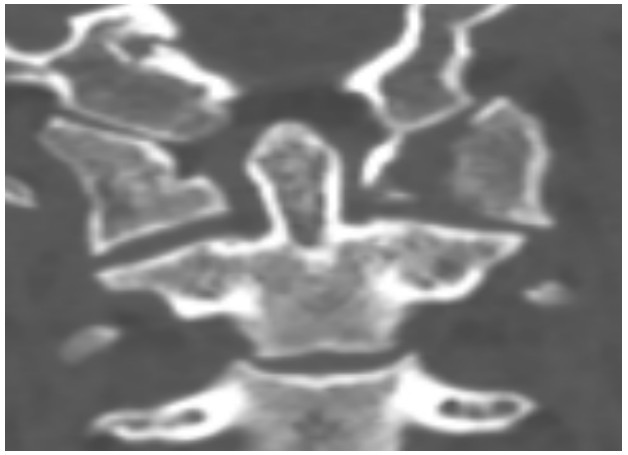

國慶節(jié)前一天,譚女士不幸被門框砸傷頸部,劇烈的疼痛和頸椎的活動受限讓她的世界瞬間陷入了黑暗。在經(jīng)歷了初步的檢查后,譚女士被診斷為寰椎骨折,這個診斷如同一道晴天霹靂,讓她和家人的心沉入了谷底。絕望中,譚女士被緊急轉(zhuǎn)至衡陽市中心醫(yī)院骨科一區(qū)(脊柱外科),錢軍博士及其團隊在接到這一緊急病例后迅速接診,經(jīng)過細(xì)致的病史詢問、體格檢查和影像學(xué)資料分析,確診譚女士的寰椎骨折伴有寰樞椎體不穩(wěn)定,迫切需要手術(shù)治療以恢復(fù)其穩(wěn)定性??紤]到上頸椎手術(shù)的高風(fēng)險性,特別是寰樞椎周圍結(jié)構(gòu)復(fù)雜,緊鄰椎動脈和脊髓,手術(shù)過程中的任何微小失誤都可能導(dǎo)致災(zāi)難性后果,錢軍博士團隊頂著壓力,迎難而上,沒有絲毫猶豫,立即行急診手術(shù),投入到緊張的救治工作中。